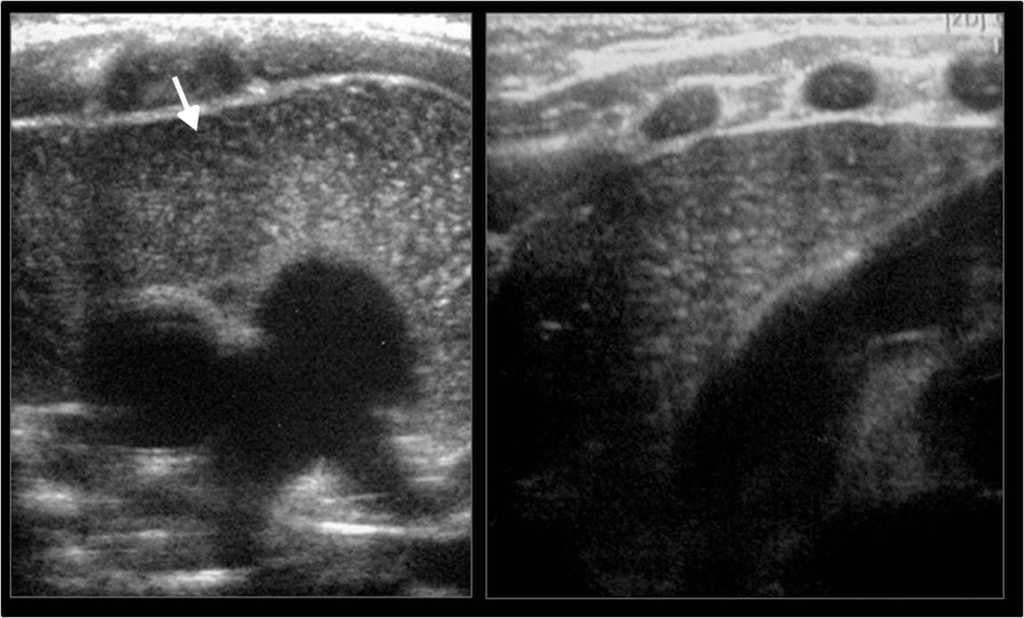

C??lico renal

Cuando hay sospecha de enfermedad liti??sica renal, las im??genes deben acompa??ar y seguir a una exhaustiva exploraci??n cl??nica16. El ultrasonido, para ello, es el primer m??todo de elecci??n porque confirma el diagn??stico de litiasis, estableciendo su tama??o y localizaci??n, excluye otras causas de dolor abdominal y confirma o descarta la hidronefrosis17. Adem??s, identifica c??lculos en los diferentes grupos caliciales, en la pelvis y en la uni??n pieloureteral o ureterovesical16 (fig. 12).

Los c??lculos se visualizan f??cilmente con el ultrasonido cuando generan sombra ac??stica posterior, pero a veces por su tama??o peque??o o el tejido circundante se dificulta su reconocimiento. En estos casos, el artefacto de centelleo en el Doppler color, consistente en la alternancia de color por detr??s de la litiasis, permite hacer el diagn??stico y aumentar la sensibilidad ecogr??fica en b??squeda de litiasis18 (fig. 13)